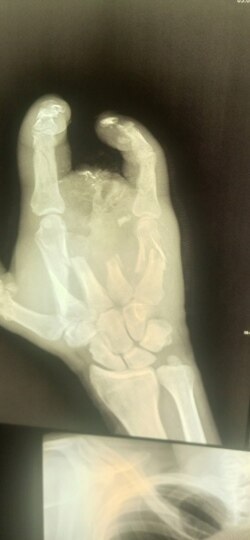

Рука Алексея после ранения на войне

Оказалось, что с незажившими ранами покалеченного солдата отправили в гражданское медучредждение для того, чтобы на руках у него не было документов из военного госпиталя. И сейчас Алексей не может доказать, что стал калекой в бою.

– Прописали мази и перевязки. Я засомневался, что лечение нормальное, благо, был знакомый хирург. Я пришел к нему и очень вовремя – началось загноение на обрубке руки. Там он уже сделал все заново – чистка, вставил спицы и даже часть кости восстановить смог. Конечно, все за деньги. Всю "зарплату", что получил за войну, считай, все на хирурга и ушло! В итоге вышел "в минус", – подытоживает Алексей.

Протез Алексей пытается получить с начала 2023 года.